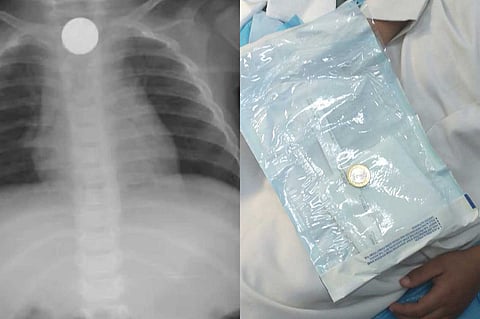

نجح فريق طبي بمستشفى المهد العام، في استخراج قطعة معدنية من أعلى مريء طفل يبلغ من العمر 6 سنوات، في عملية استغرقت 4 دقائق فقط.

وأوضح الفريق الطبي أن الطفل قدِم إلى طوارئ المستشفى وهو يشتكي من بلع جسم غريب (قطعة نقود معدنية) كانت قد عَلِقت في أعلى المريء؛ ما تَسَبَّب في حالة اختناق وعدم القدرة على البلع.. عندها قرر الفريق الطبي إجراء عملية عاجلة، واتضح أنها قطعة معدنية نقدية «فئة الريال».

وتمت العملية بنجاح، ودون حدوث مضاعفات؛ حيث غادر الطفل المستشفى وهو بصحة جيدة.